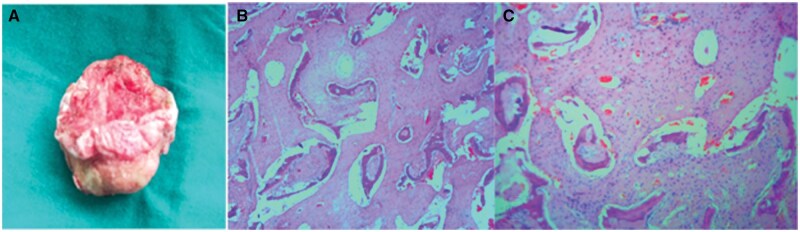

Fibrous dysplasia (FD) is a benign condition affecting osteoblasts, which fail to undergo proper differentiation and maturation, resulting in the replacement of normal osteoid matrix with ground glass fibrous tissue. Aneurysmal bone cyst (ABC) is a benign, expansile, lytic lesion characterized by multiple blood-filled cystic cavities containing haemorrhagic products at varying stages. Secondary ABC arising from craniofacial FD is extremely rare. To date, only 10 cases have been reported in the literature. This report highlights the clinical presentation, imaging findings, and histopathological confirmation of a secondary ABC in a patient with polyostotic craniofacial FD.